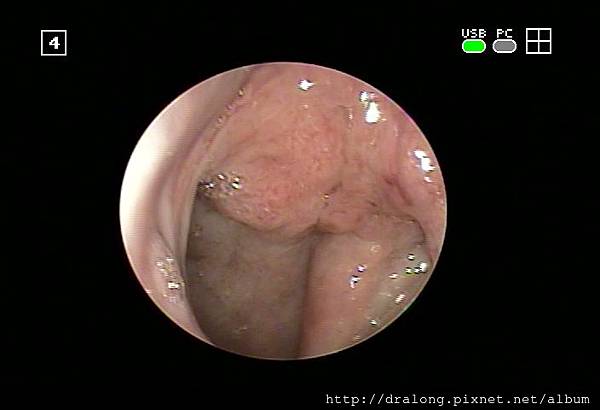

急性鼻咽發炎